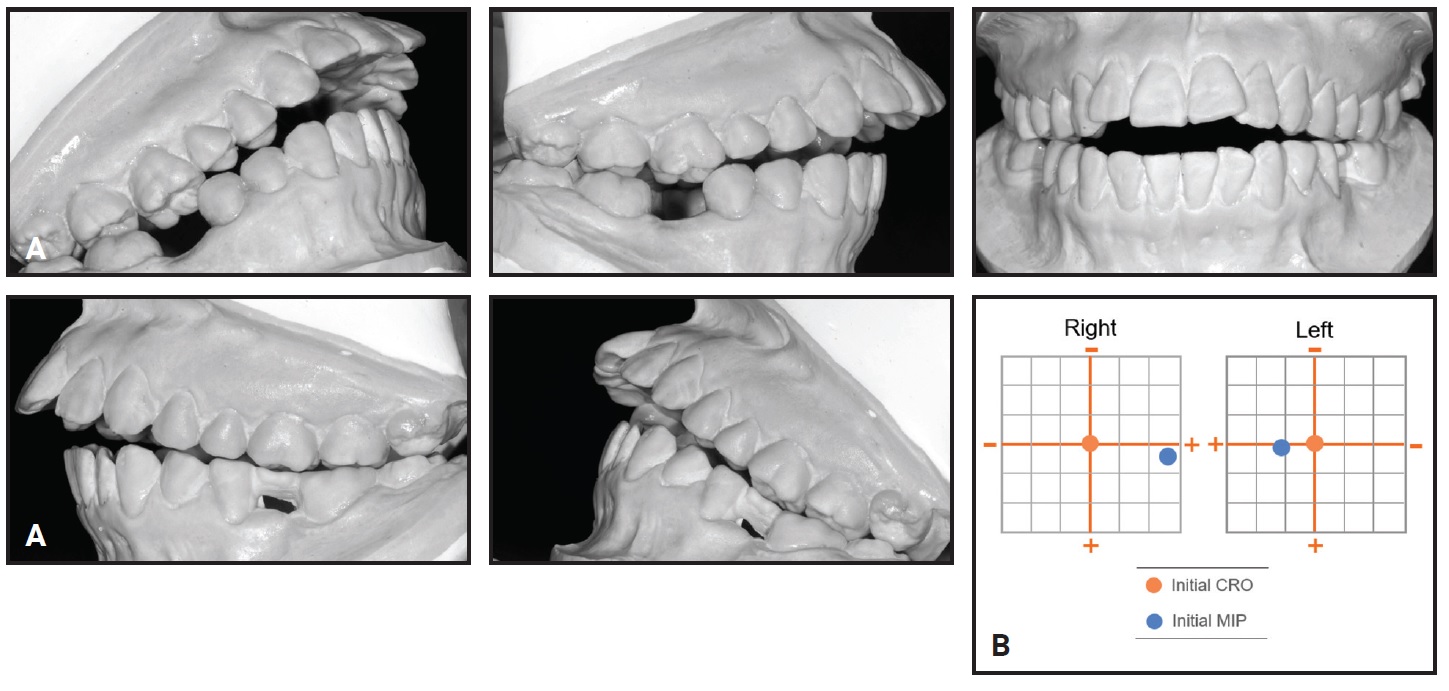

Total treatment time was 35 months (Fig. 5). The balanced profile and Class I canine and molar relationships were successfully maintained, and the patient was highly satisfied with his teeth and profile. The mandibular incisors were aligned, with the proper torque. The skeletal maxillomandibular relationship was slightly improved, the maxillary incisors were slightly proclined, and the mandibular incisors were uprighted (Table 1). The overjet and overbite were reduced, and the upper and lower lip positions and nasolabial angle were basically unchanged.

Fig. 5 Patient after 35 months of treatment (records taken seven months later).

Post-treatment dental cast measurements of the WALA ridge were increased by 5mm at the mandibular canines and 2.5mm at the first premolars10 (Fig. 6).

Fig. 6 A. WALA ridge10 before treatment. B. After treatment.